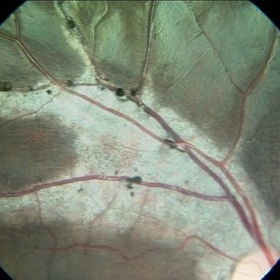

Choroidal Osteoma With CNV- Aautofluorescence

Feb 28 2024 by stephen oconnell

23 year old male with 10 months of vision loss prior to presentation. Clarus 700 autofluorescence image.

Condition/keywords: macular choroidal osteoma